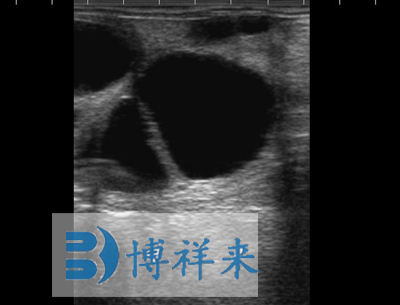

可换探头,可配备:128振元(5-8MHZ)直肠探头、128振元凸阵(2.5-5MHZ)直肠探头、128振元微凸探头以及特殊探头、支持3.5兆赫至7.5 MHz扇形探头等 支持用户可选择探头扫描方向 |